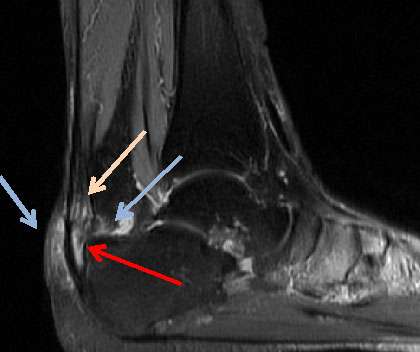

MRT

Abbildung 4: Das MRT des Rückfusses zeigt die unterschiedlichen Veränderungen, die mit einer Insertionstendinopathie einhergehen. Die präachilläre und retrocalcaneare Bursitiden (Pfeile) kommen zur Darstellung, sowie die intratendinösen Veränderungen.

Abbildung 4

Das MRT stellt den Goldstandard bei der Beurteilung von Sehnen und Weichteilgeweben dar. Die optimalen Sequenzen hängen häufig von dem verwendeten Gerät ab, zumeist werden jedoch T1-gewichtete und flüssigkeitssensitive STIR sowie Fett supprimierte intermediär gewichtete Sequenzen in axialer und sagittaler Schnittführung durchgeführt 12.  Das MRT ermöglicht insbesondere den Nachweis von intratendinösen Veränderungen und ansatznahen Partialrupturen. Daneben können im MRT das Paratenon, die ansatznahen Bursen und auch die differerentialdiagnostisch in Frage kommenden Strukturen wie die FHL-Sehne und das Os trigonum mitbeurteilt werden. Ein Ödem in der Tuberositas des Calcaneus kann degenerative Veränderungen der Gleitfläche zur  Achillessehne hin anzeigen. Aufgrund der Schnittführung und des zum Teil geringen Kontrastes ist die Identifikation und Lokalisation von Ossifikationen jedoch gelegentlich zur operativen Planung nicht ausreichend (Abb 4).